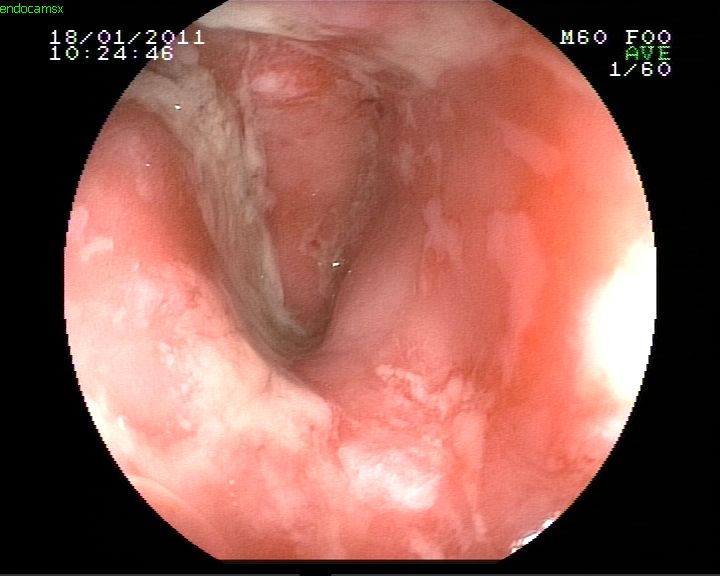

Ülseratif kolit